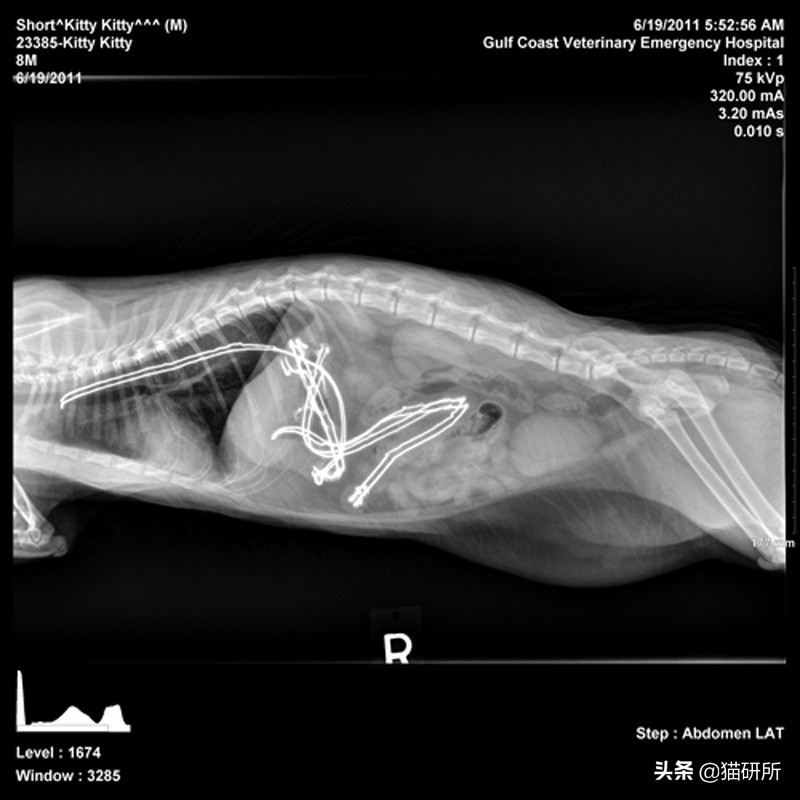

误食多根线状物

如果说偶尔误食一根细线或许还能侥幸排出,那么误食较多线状物的后果就严重多了。

美国一只叫Winnie的猫咪渐渐不吃不喝也不去厕所,家人带去医院检查后发现它误食了46根发圈。

经过手术治疗后,猫咪恢复了健康。图自:reddit